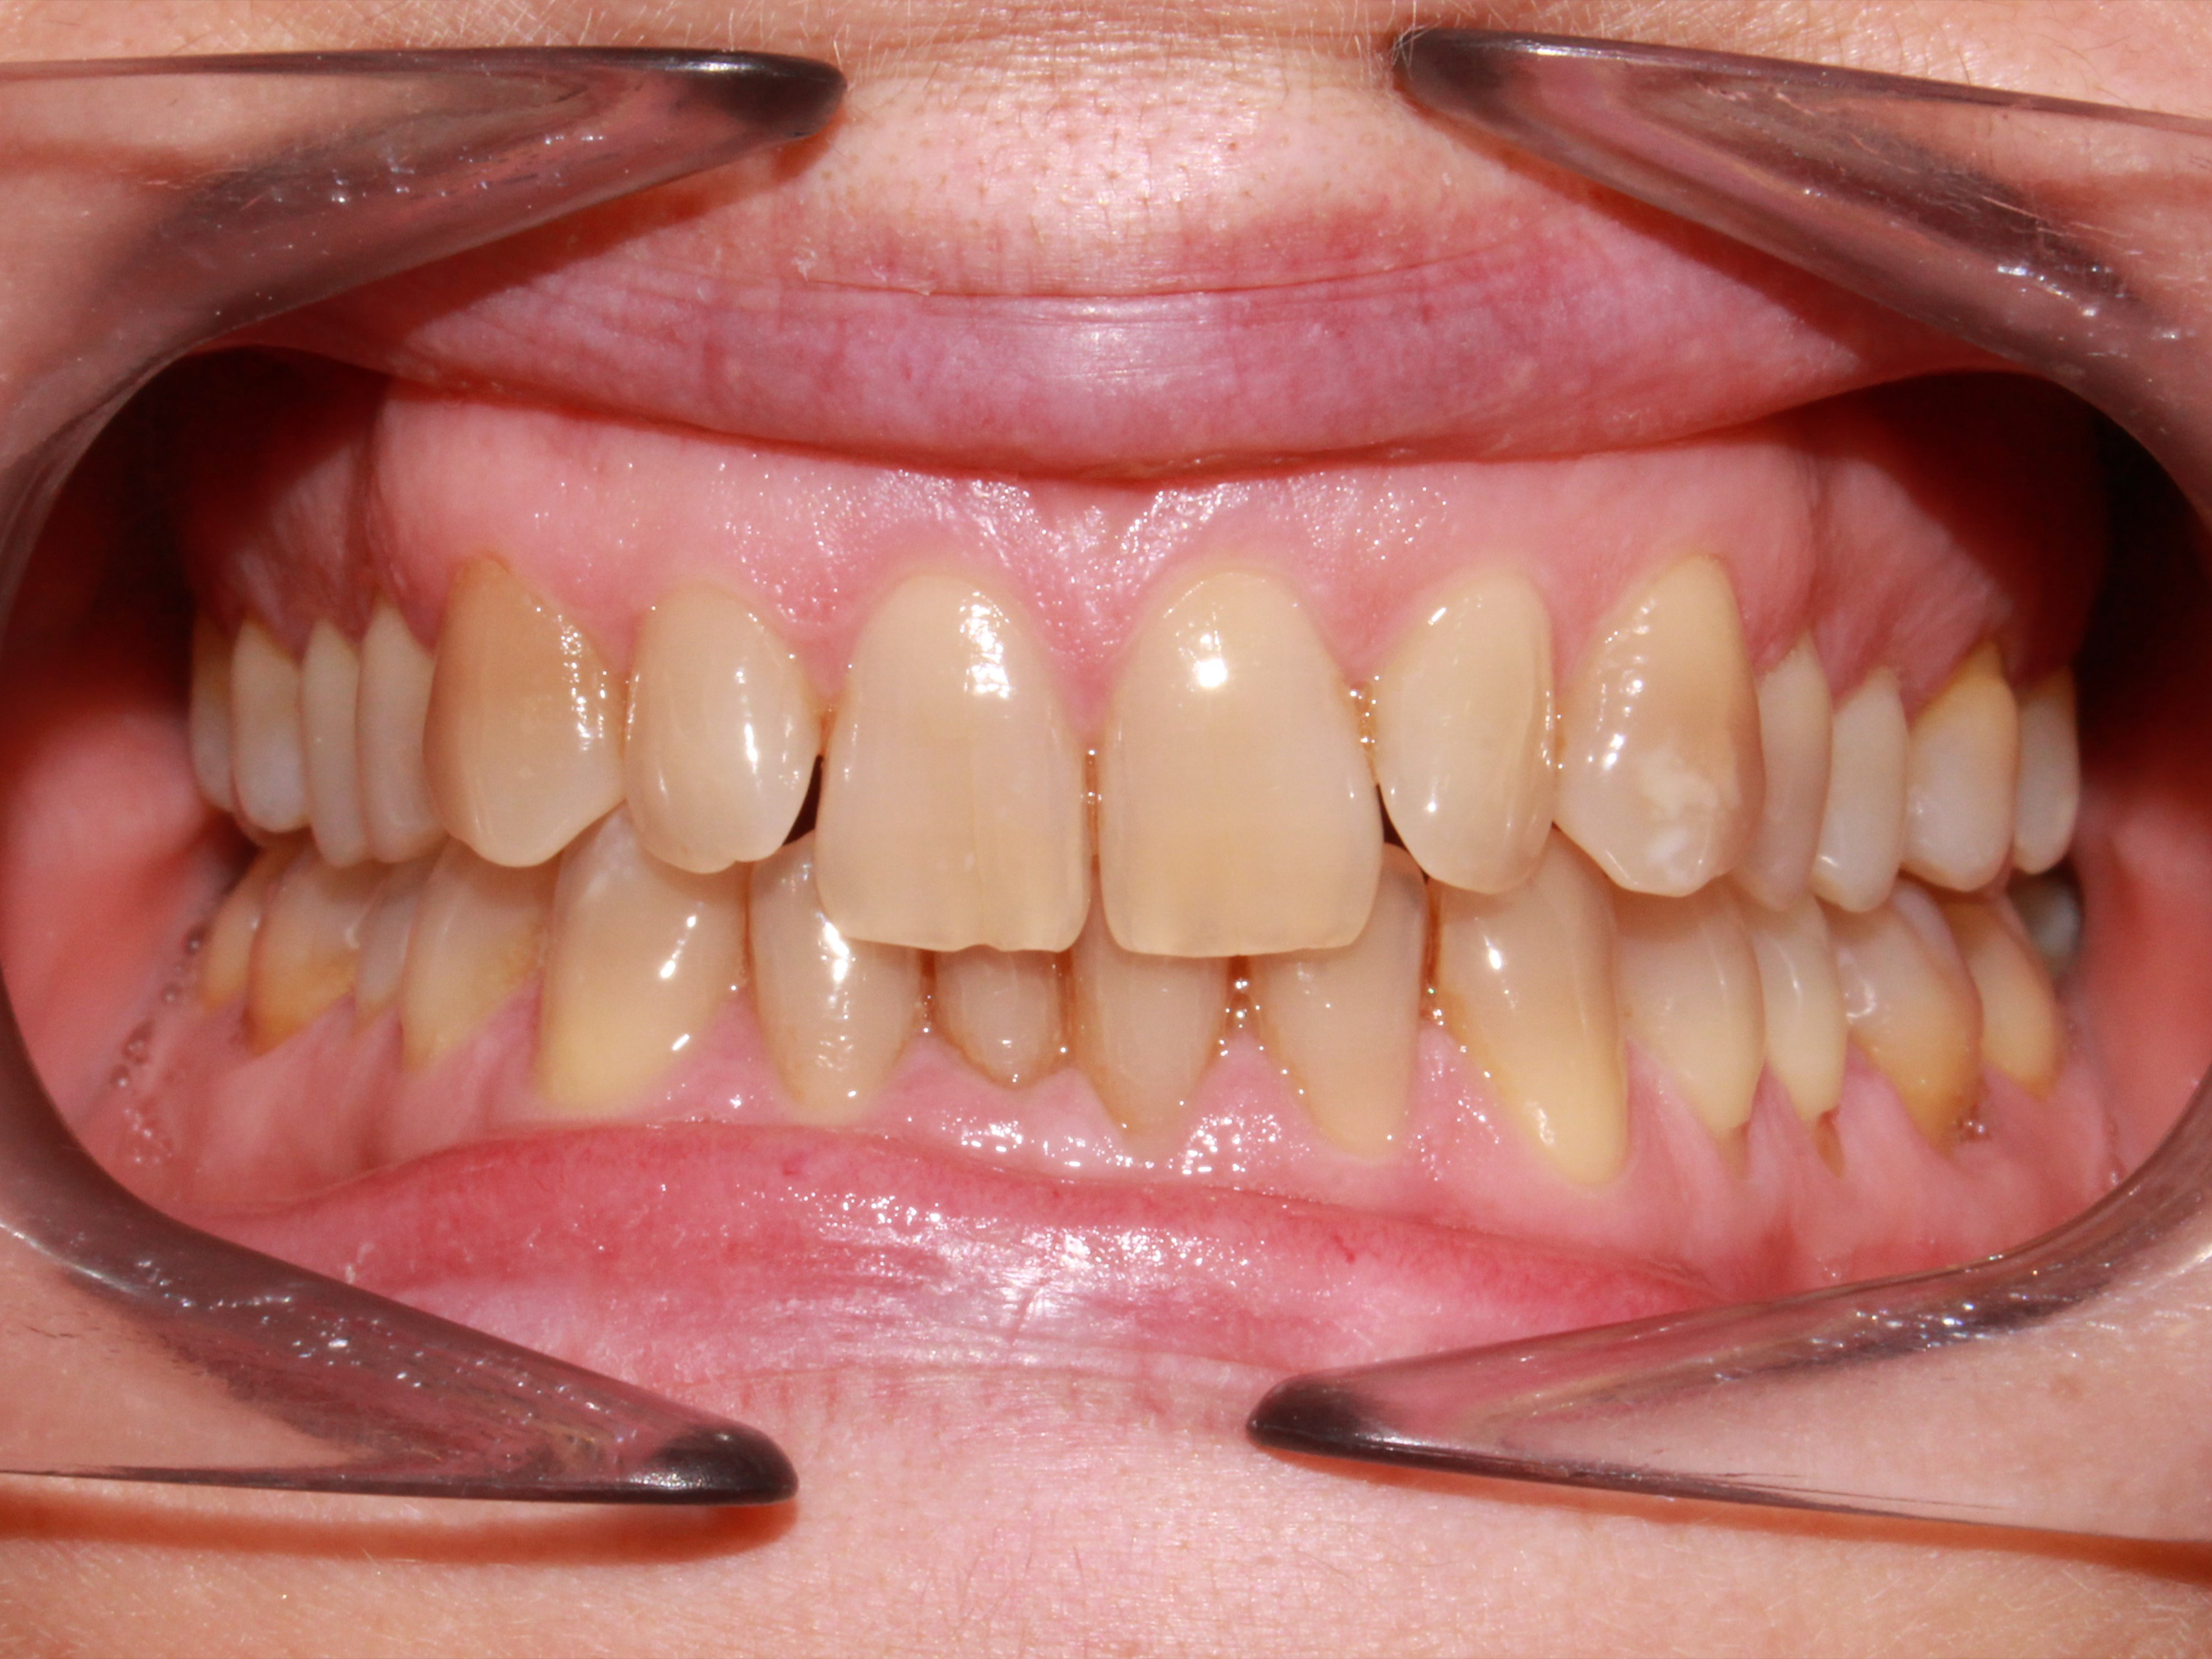

This article describes a treatment with spark aligners performed in a 52-year-old patient, who presented at the time of consultation with an increased overbite, moderate crowding in both arches, gingival smile and a clear alteration in the color of the enamel due to environmental factors.

The protocol applied for the present treatment plan was based on the transversal development of the arches at the expense of expansion at the expense of correction of posterior and anterior torques in the following way:

BiteRamps were added on upper teeth 2-2 to assist the programmed intrusion movement of both anterior sectors (upper and lower). A Spark20 treatment plan was chosen using all active aligners and TruGen material and aligner replacement every 7 days.